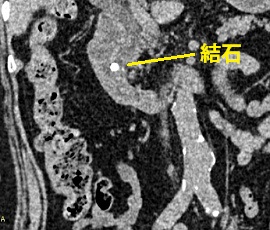

急性腹症にて救急受診。精査の結果、総胆管結石と診断。腹腔鏡下胆管切開結石除去術(胆嚢摘出術含む)を施行した。

CT画像